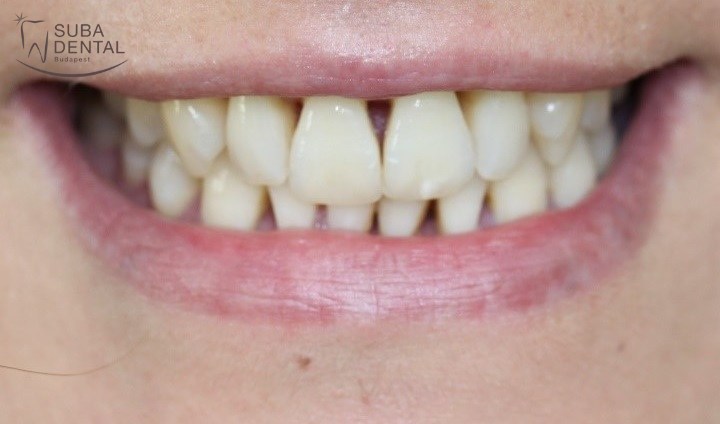

Előtte

Utána